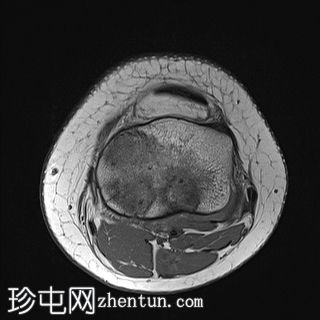

轴位PD序列

脂肪抑制序列

轴位

T1加权像

关节内大量积血,可见血细胞比容增高征。股骨外侧髁前部及髌骨内侧可见挫伤性微骨折。髌骨内侧支持带及髌股内侧韧带水肿增厚。髌骨内侧关节面下关节软骨浸润,提示I期骨软骨损伤。

髌骨外侧隐窝可见游离体,其信号强度与关节软骨一致,提示髌骨关节软骨外剥离损伤。股骨滑车和股骨关节软骨正常。

胫骨近端和腓骨骨骺以及股骨远端延伸至干骺端的骨骺周围可见局灶性骨髓水肿。这些提示存在局灶性骨骺周围水肿区。

十字韧带和侧副韧带正常。半月板正常。股四头肌腱和髌腱正常。

该病例具有短暂性髌骨外侧脱位复位损伤的特征性表现,包括预期的骨挫伤模式、内侧髌骨支持带/内侧髌股韧带损伤、髌骨骨软骨损伤以及髌骨软骨游离体。